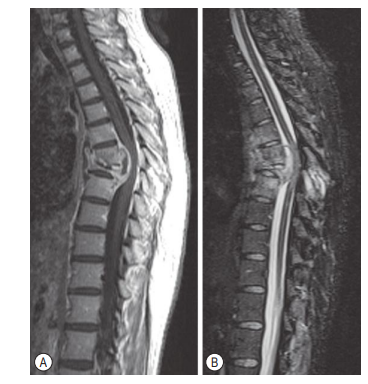

Q

A 19-year-old male presents with neck pain, fever, and numbness in his legs and trunk up to his arm pits. His neurological examination is consistent with an upper motor neuron lesion, and you note a small midline sinus on the back of his neck. Blood cultures grow

Streptococcus epidermis, T1 MRI with contrast is shown. Which one of the following is the next appropriate step?

a. MRI head with contrast

Intramedullary spinal cord abscesses (ISCAs) are

rare, and patients are young. ISCAs occur

throughout the spine, but they are most frequently found in the thoracic region. The pathogenesis of ISCA can be divided into two broad

categories: hematogenous spread and direct

implantation. The more complex of the two is

hematogenous spread via arterial supply (septic

emboli), venous drainage (increased intrathoracic/abdominal pressure causing backflow in low pressure spinal venous system), or lymphatics (draining mediastinum, abdomen connect with Virchow Robins paces in spinal cord

via channels in spinal nerves). The most common primary infection is pulmonary, endocarditis, urinary tract infections, peritonitis, and

peripheral skin infections. The other major

route for the pathogenesis of ISCA is direct

implantation via a congenital midline neuroectodermal defect (e.g. dermal sinus tract), postoperative, after penetrating trauma. Most

commonly no cause is found (cryptogenic).

Causative organisms are Staphylococcus and Streptococci, with other significant organisms Actinomyces, Proteus mirabilis, Pneumococcus, Listeria monocytogenes, Hemophilus, and Escherichia coli. Cases of contiguous spread via a dermal sinus tract are most commonly due to Staphylococcus epidermidis, S. aureus, Enterobacteriaceae, anaerobes, and Proteus mirabilis. Postsurgical (contiguous) cases are most often due to S. epidermidis,

S. aureus, Enterobacteriaceae, and Pseudomonas

aeruginosa. The cases that arise from hematogenous spread reflect the site of primary infection.

The presenting signs and symptoms in patients

with ISCAs almost always involve motor deficits,

sensory impairment, loss of sphincteric control,

pain, and fever. Acute infections (<2 weeks) partial transverse myelitis commonly associated

with fever and leucocytosis, while subacute

(2-6 weeks) and chronic (>6 weeks) present like

intramedullary tumors. Investigations include

WCC, CRP, ESR, CSF analysis (usually

negative unless meningitis). Imaging of choice

is contrast MRI which may differentiate between

early and late myelitis. CT myelography may

show widening of the cord at a focal segment

with obstruction to CSF flow. X-rays are usually

normal at presentation. Other features are osteomyelitis, spinal deformity, spinal stenosis, and spinal dysraphism, current recommendations

are for immediate surgical treatment. The surgery should include laminectomies at the

involved levels, intradural exploration, midline

myelotomy, and irrigation and drainage of the

abscess cavity. Aggressive treatment with antibiotics requires empirical therapy until an

organism has been isolated. The choice of antibiotics for empirical therapy should be based on the suspected source of infection and then

adjusted on the basis of the operative culture

results. The current recommendation is a minimum of 4-6 weeks of parenteral therapy.

Patients presenting with acute symptoms have

a worse prognosis in terms of neurologic recovery. Overall, the death of a patient diagnosed

with an ISCA is most frequently due to the presence of multiple CNS abscesses and, specifically, to brain or brainstem abscesses.